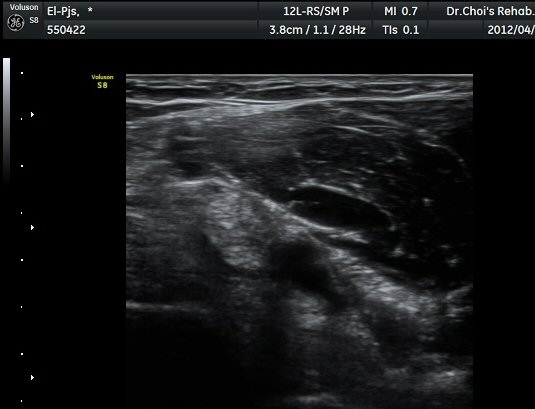

ŽÃËÀÚ¸¦ ÆÈ²ÞÄ¡ ¸»´ÜÀ¸·Î À̵¿ÇÏ´Ï À̵ιڱ٠ÈûÁÙÀÇ ºñÈÄ¿Í ÈûÁÙ ÁÖÀ§¿¡ Àú¿¡ÄÚ ¼ö¾×Àú·ù°¡ ]

°üÂûµÈ´Ù(±×¸² 2, 3, 4, 5). ŽÃËÀÚ¸¦ ¸»´ÜÀ¸·Î À̵¿ÇÒ ¶§ ŽÃËÀÚ¸¦ ¸Ó¸®ÂÊÀ¸·Î °æ»ç(tilting)½ÃÄѾß

À̵ιڱ٠ÈûÁÙ¿¡ Á÷°¢ ÀÇ ÃÊÀ½ÆÄ Á¶»ç°¡ °¡´ÉÇÏ¿© À̵ιڱ٠ÈûÁÙÀÌ °í¿¡ÄÚ·Î °üÂûµÈ´Ù.

À̵ιڱ٠ÈûÁÙ Á¾´Ü¸é°Ë»ç¿¡¼­ ÈûÁÙÀÇ ºñÈİ¡ °üÂûµÇ³ª ÈûÁÙÀÇ ¿ä°ñµ¹±â(radial tuberosity)

ºÎÂøºÎ´Â ºñµî¹æ¼ºÀΰøÀ½¿µ(anisotopic artifact) ¶§¹®¿¡ ¶Ñ·ÈÈ÷ °üÂûµÇÁö ¾Ê´Â´Ù(±×¸² 6).